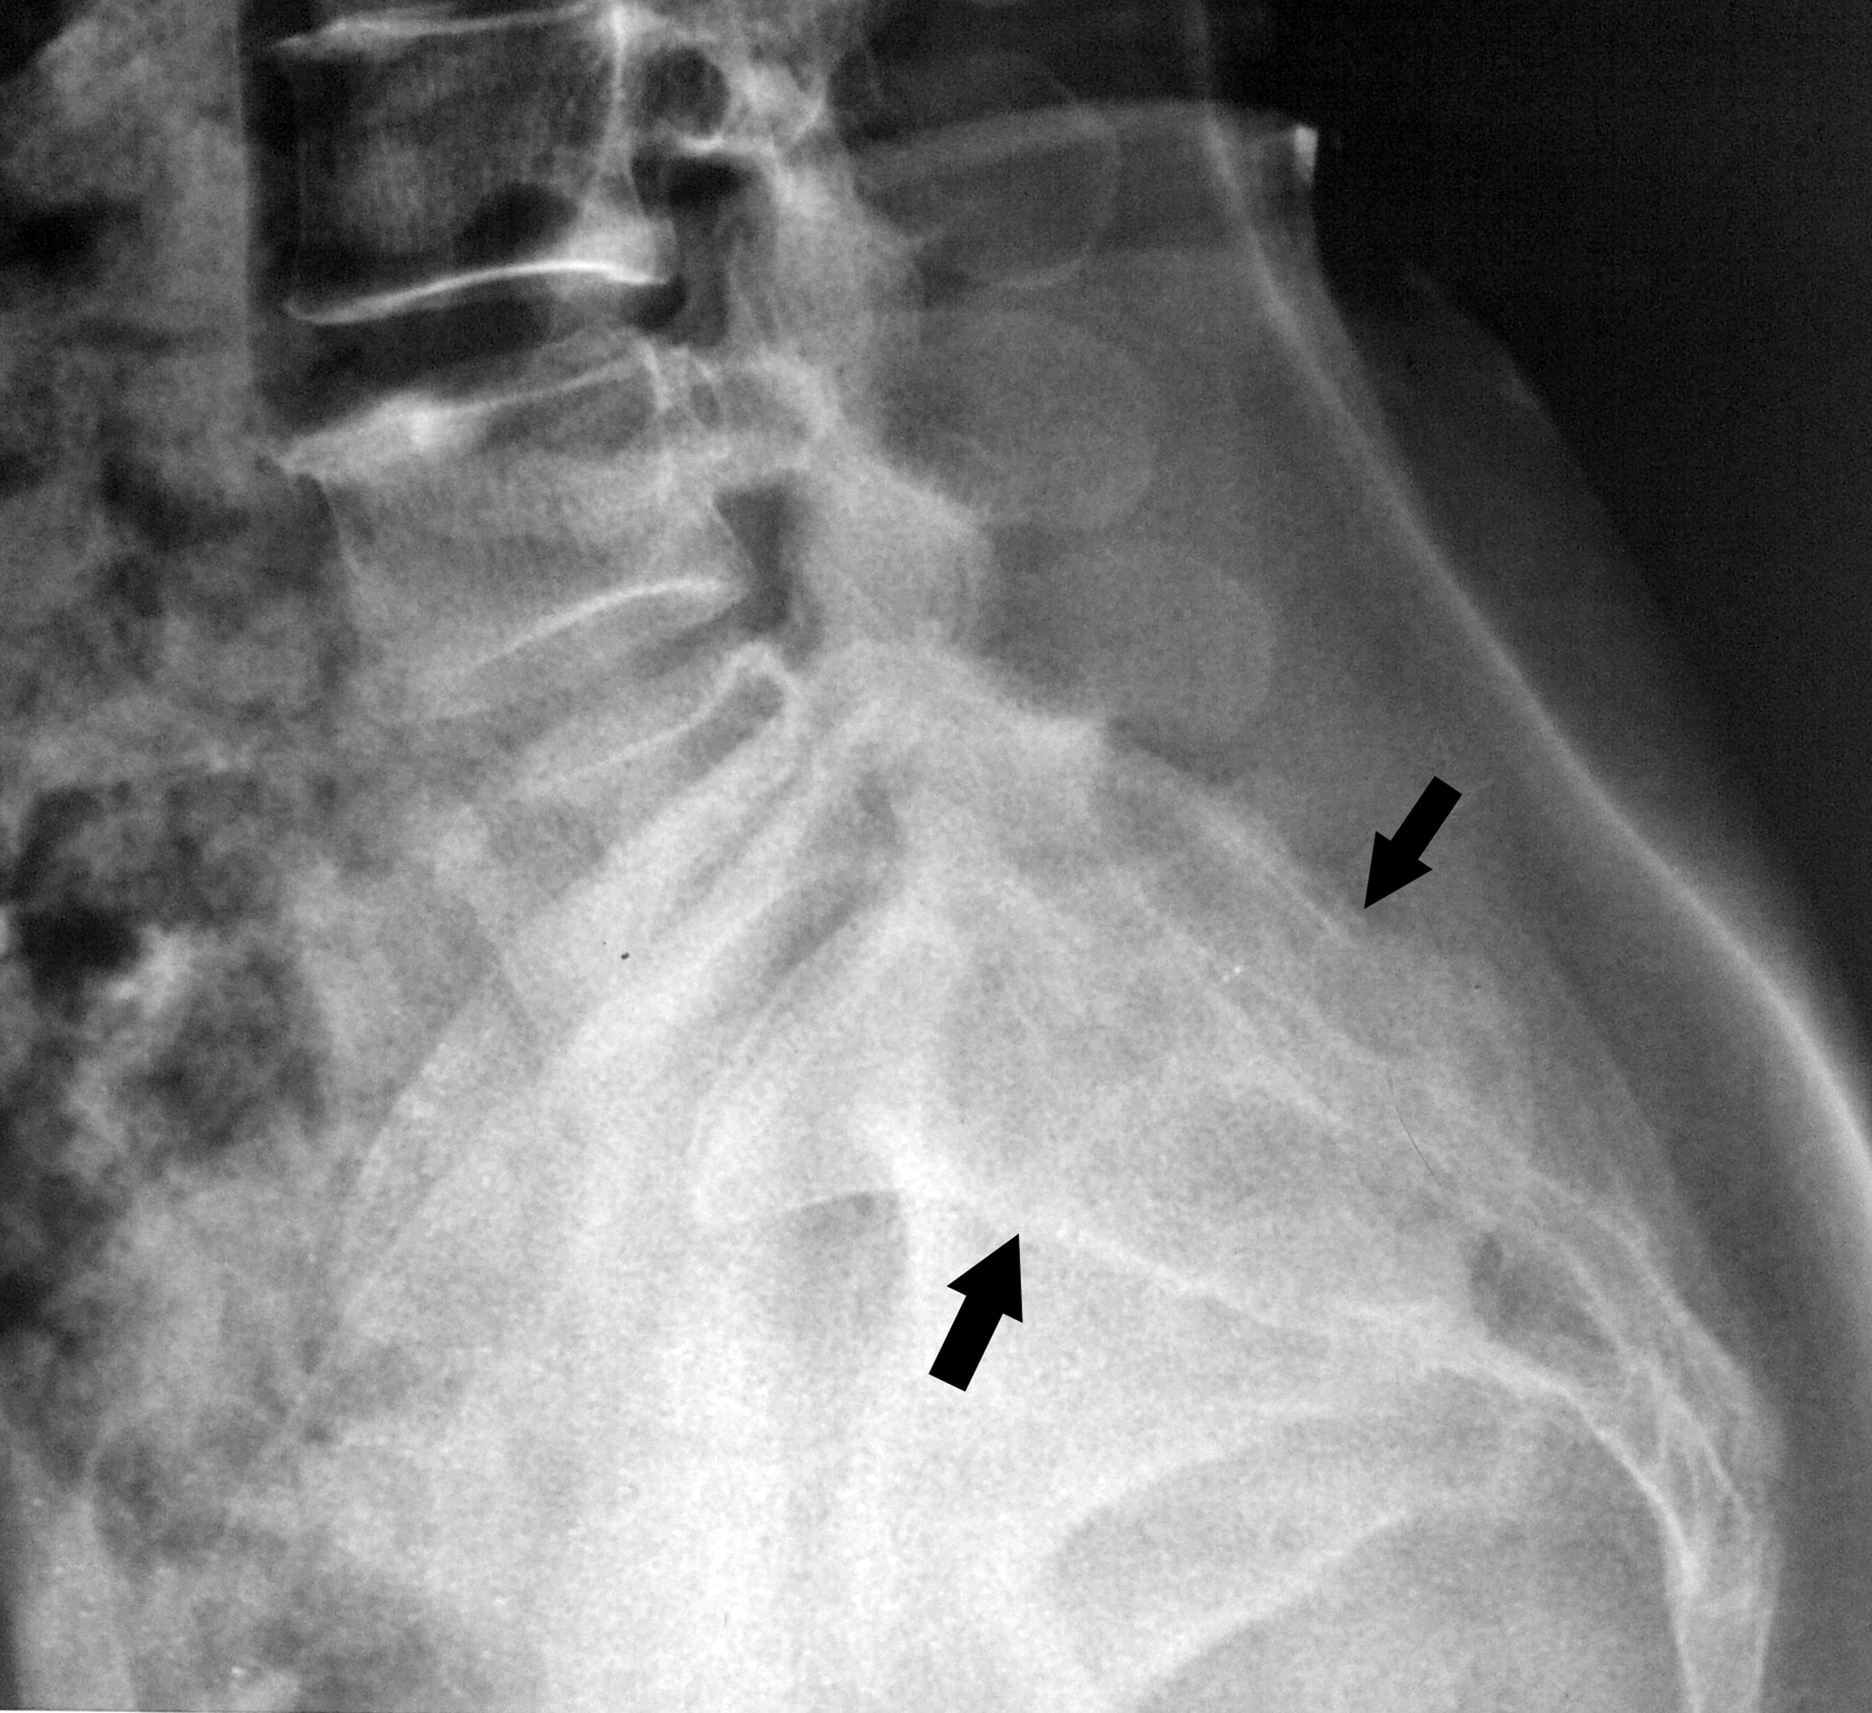

Sacral arachnoid cyst presenting as chronic low back pain

perineural cyst, sacral Tarlov cyst, spinal arachnoid cyst, arachnoid cystAbstract

Bangladesh Journal of Medical Science Vol.14(1) 2015 p.106-108